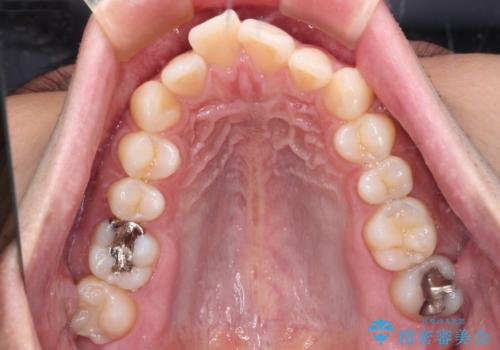

- 口元の突出感と下の前歯のがたつきを主訴として来院された患者様です。

口元の突出感と叢生改善のため上下左右の第一小臼歯4本を抜歯し、ワイヤー装置にて矯正治療を行うこととしました。

なるべく目立たない装置が希望だったため、審美装置で治療を行いました。